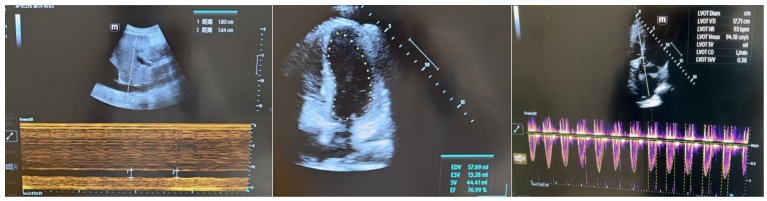

床旁超声提示患者心脏功能良好,左右心比例协调(1)综合超声(1)和相关化验结果,判断患者为脓毒性休克(分布异常性休克)

1  患者血流动力学参数

1  患者超声检查结果

右肺中叶开口再次送检BALF mNGS(Free)高侧卧位、加强胸部物理治疗和液体管理。复查BNP正常, 射血分数大于50%, 近3液体负平衡, 肺部超声未见大量B线

膈肌超声显示:隔肌厚度0.18 cm,膈肌厚度变化率为10%,膈肌活动度为0.94 cm(图6)。膈肌功能评估提示膈肌活动度减弱;自主呼吸试验(SBT)无法通过,预估短时间拔除气管插管困难,遂予气管切开。

图片

6  患者膈肌超声